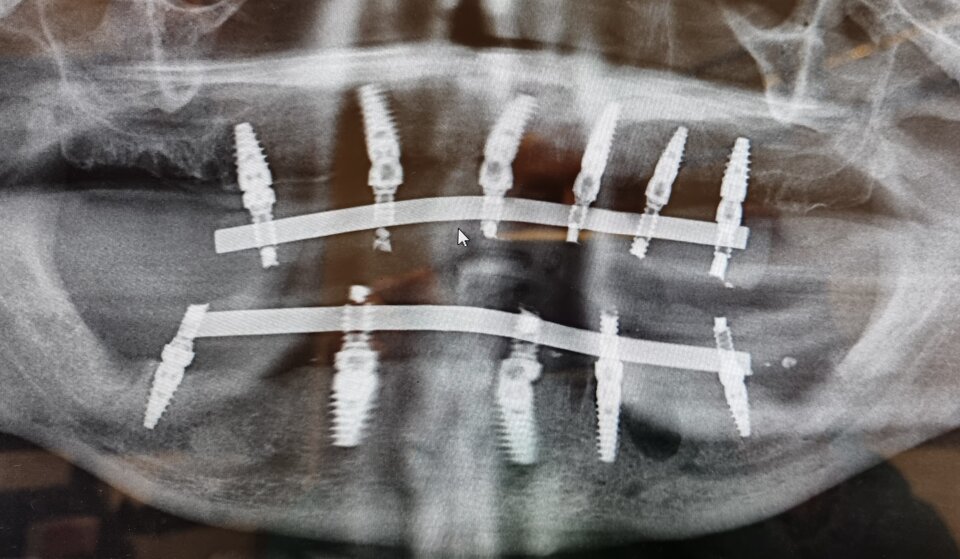

La tecnica più usata al giorno d'oggi si chiama ALL ON FOUR oppure ALL ON SIX e prevede la realizzazione di una intera arcata composta di dodici ( più raramente quattordici) denti fissi montati su una barra in titanio che verrà fissata su 4 o 6 impianti inseriti nell'osso ( da cui il nome).

IMPIANTI A CARICO IMMEDIATO

Si parla di implantologia a carico immediato quando subito dopo l'inserimento dell'impianto in titanio nell'osso si avvita il moncone e su di esso si applica un dente provvisorio in resina fissato con un cemento.

QUI SOTTO UN ESEMPIO DI ALL ON FOUR DEFINITIVA A CARICO IMMEDIATO REALIZZATA NELLO STESSO GIORNO